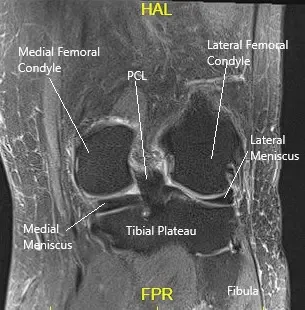

La resonancia magnética de la rodilla izquierda sugirió un desgarro meniscal medial y defectos en el cartílago articular del compartimento medial y patelofemoral.